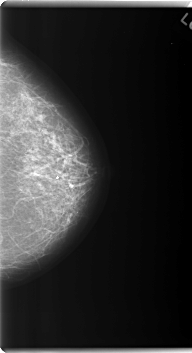

C_0179_1.LEFT_MLO

C_0179_1.LEFT_CC

LEFT_MLO LINES 5960 PIXELS_PER_LINE 3416 BITS_PER_PIXEL 12 RESOLUTION 50 NON_OVERLAY

LEFT_CC LINES 6000 PIXELS_PER_LINE 3256 BITS_PER_PIXEL 12 RESOLUTION 50 NON_OVERLAY